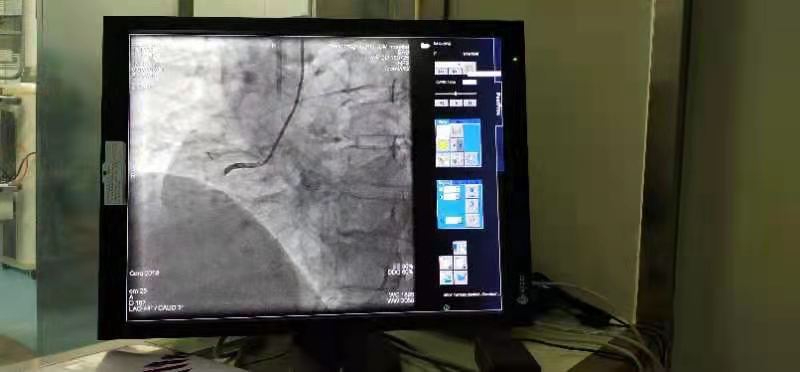

1月14日下午,在鄲城縣第二醫(yī)療健康服務集團鄲城縣中醫(yī)院心病一區(qū)手術(shù)室,經(jīng)過充分的術(shù)前準備,集團總醫(yī)院副院長、心病一區(qū)主任楊俊帶領團隊,為44歲的冠心病患者朱某男成功實施了心臟冠脈支架介入治療。與以往手術(shù)不同的是,患者朱某男享受到了國家集采政策后降價的冠脈支架,其植入的冠脈支架從原先每枚均價數(shù)萬元降為700元。

手術(shù)的順利完成,也標志著首批國家集中采購的醫(yī)用耗材冠脈支架在我院正式落地實施。

科室主要開展冠心病、心肌梗死、高血壓病、心肌病、心力衰竭、心律失常等心血管疾?。?013年與鄭州大學一附院聯(lián)合首家開展冠脈介入支架植入術(shù),填補鄲城縣冠脈介入空白,相繼首家開展射頻消融術(shù),并帥先開展急性心肌梗死溶栓治療。2018年9月在中國胸痛中心官網(wǎng)已注冊申請并全院開展胸痛中心建設。自2013年以來,與鄭州大學一附院聯(lián)合開展冠心病介入治療數(shù)千例,效果顯著,在社會上享有較高的榮譽。